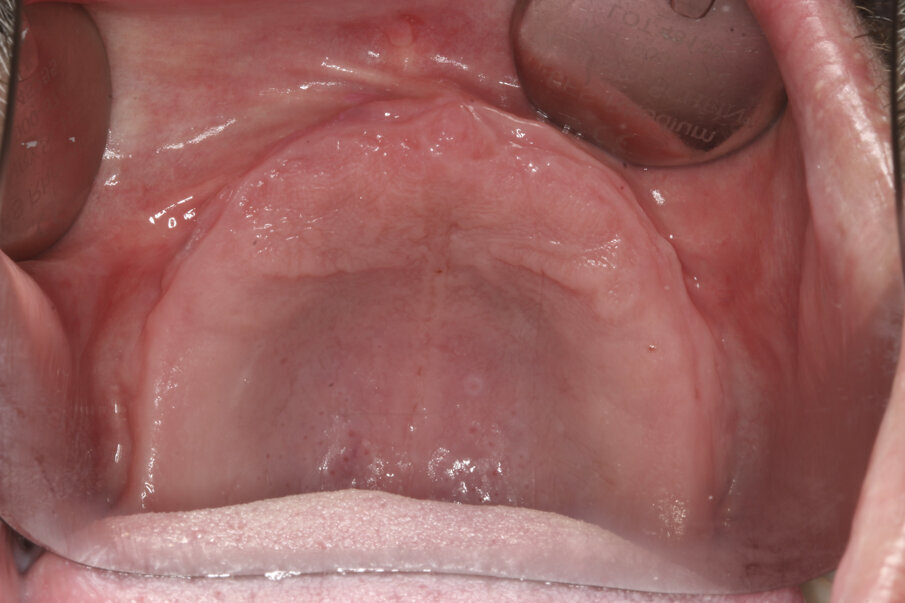

A 55-year-old male patient complained about the retention of his maxillary complete denture and requested a fixed solution. Intra-oral examination and radiography confirmed an edentulous maxilla (Figs. 1 & 2).

Fig. 1: Pre-op situation of the edentulous maxilla.